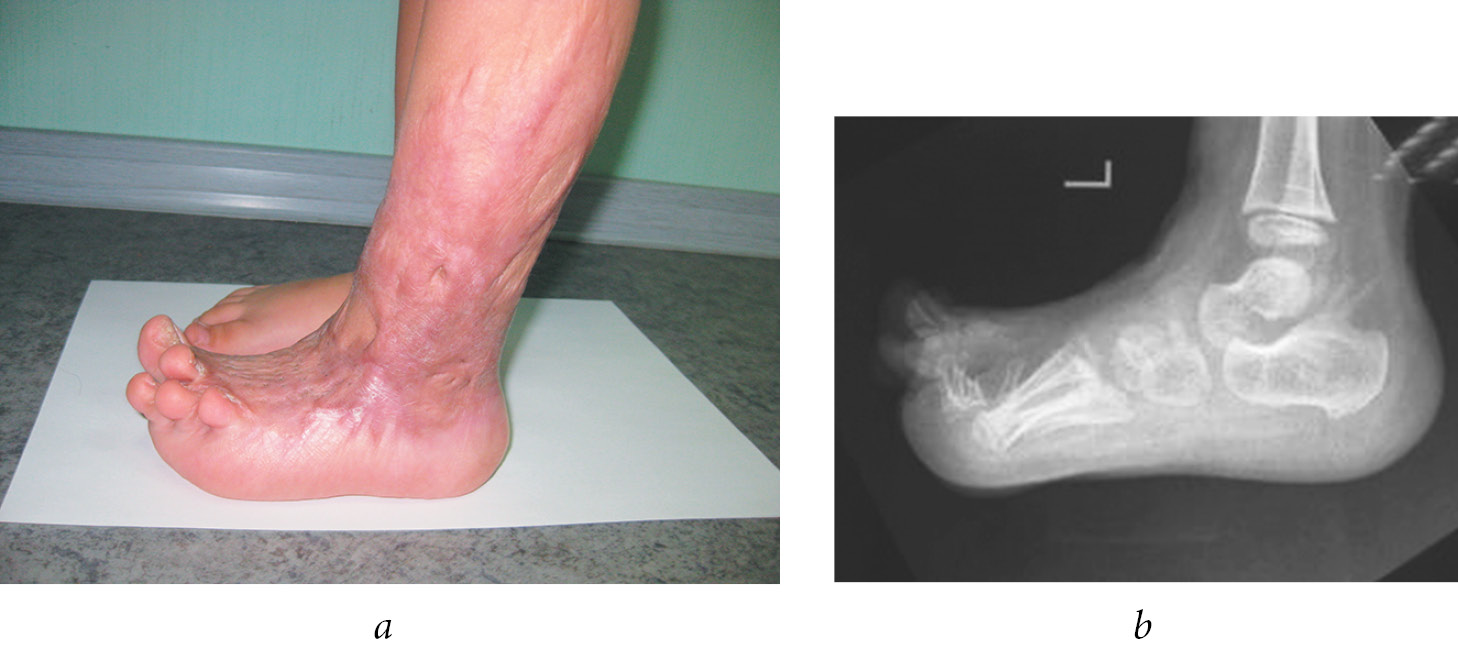

In some cases, surgery with sieve skin autografts resulted in the development of multiplanar foot deformities, which required long-term and multi-stage surgical treatments. In Fig. 7, a hypertrophic scar of the lateral surface of the foot, ankle joint and lower leg led to progressive lateral forefoot displacement. The long-term growth of the foot under conditions of asymmetrical cicatricial traction can cause critical consequences that cannot be completely eliminated.

Fig. 7. Images of a 2.5-year-old patient diagnosed with extensor-abduction cicatricial contracture in the metatarsophalangeal joints III, IV, and V of the right foot 1.5 years after skin restoration using a sieve skin autograft. a, b — hypertrophic scar on the outer surface of the right ankle joint, lateral displacement of the forefoot (clinical presentation); c — dislocation in the metatarsophalangeal joint V (X-ray image)

Figure 8 shows a severe equino-valgus-abduction deformity of the foot in a 7-year-old child due to a shortened scar that passes from the external arch of the foot to the lateral surface of the ankle joint.

Fig. 8. Images of a 7-year-old diagnosed with multiplanar cicatricial deformity of the left foot 5 years after grafting the granulating wound of the lower leg and ankle joint with a sieve skin autograft. a — a shortened hypertrophic cicatricial cord along the edge of the established sieve skin autograft (clinical presentation); b — lateral displacement of the fore part of the left foot (clinical presentation); c — radiographic image showing supination decentration of the talus bone, rotational and equinus dislocation: complete dissociation of the talus and calcaneal bones at the level of the anterior articular facet, the forefoot in a pronounced supination position consensual with the calcaneal bone, the navicular bone is articulated with the medial-plantar surface of the head and neck of the talus bone

The long-term lateral cicatricial traction led to a gradual lateral displacement of the bones of the ankle, subtalar, and calcaneocubital joints, which progressed to the transverse tarsal joint and the tarsometatarsal joint, resulting in a multiplanar hindfoot and midfoot deformities. The active load on the gradually deforming foot accelerated fibrosis of the ligaments and joint capsules, the development of secondary deformities in the tarsal bones, and the progression of disorders in spatial relationships in the joints.